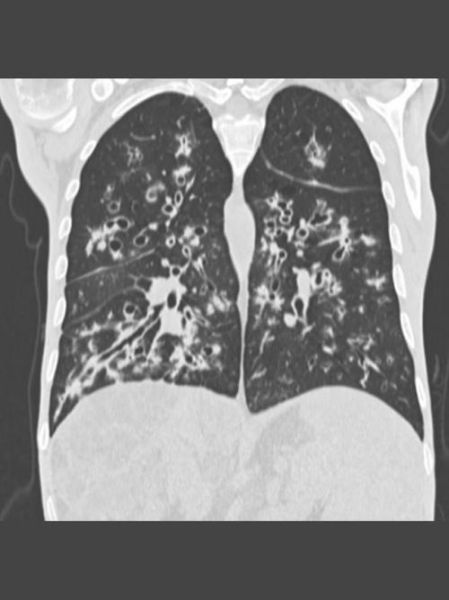

(图片来源网络,侵删)

抗感染策略升级:从“轮番轰炸”到“精准打击”

铜绿假单胞菌是CF患者肺衰竭主因。传统做法是长期吸入妥布霉素,但耐药率逐年攀升。